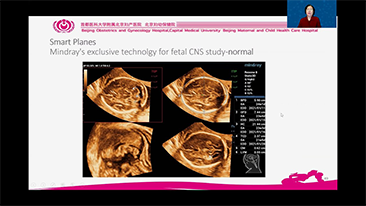

Zoptymalizowane schematy post?powania w badaniach ginekologicno-po?o?niczych s? niezb?dne, aby obs?u?y? du?? liczb? wizyt przesiewowych w poradniach zdrowia dla kobiet. Dla przyk?adu deformacje o?rodkowego uk?adu nerwowego (OUN) to jedne z najcz?stszych wad wrodzonych. Ze wzgl?du na r├│?ne warunki obrazowania, takie jak niewystarczaj?co dobra pozycja p?odu, obrazowanie ?rodkowej p?aszczyzny strza?kowej (MSP, median sagittal plane) jest szczeg├│lnie trudno uzyska? na podstawie klasycznego obrazu USG 2D. Dlatego automatyczne wykrywanie i pomiary mog? znacz?co poprawi? efektywno?? skanowania.